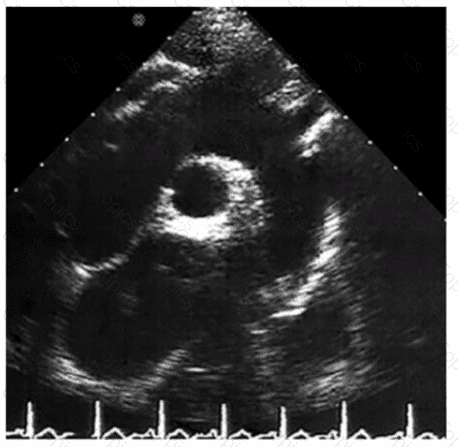

Which congenital heart anomaly is found in approximately 30% of normal adults?